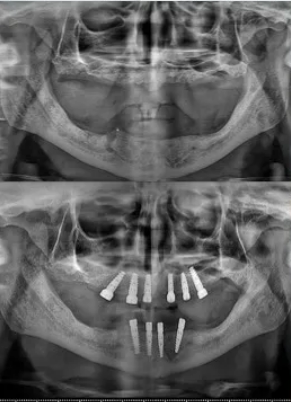

CBCT Scan Results

The scan showed us:

- Lower jaw: There was enough bone to place implants without needing bone grafts.

- Upper jaw: The bone had shrunk a lot. Only the front area had enough bone. The sinus cavities had expanded into the back areas where teeth used to be. Normally, this would need sinus lift surgery or special zygomatic implants.

Lower jaw: We placed four implants with special connectors (multi-unit abutments) to hold the teeth.

Upper jaw: We placed six implants instead of four. This gave us extra security – if one implant had a problem, the other five could still support all the teeth.